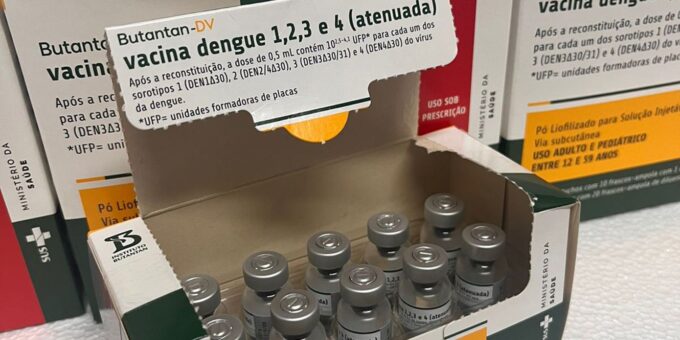

Capital paulista amplia locais de vacinação nesta semana; veja lista

8 de junho de 2026Ministério da Saúde suspende vacina contra a dengue do Butantan

Capital paulista amplia locais de vacinação nesta semana; veja lista

8 de junho de 2026Ministério da Saúde suspende vacina contra a dengue do Butantan